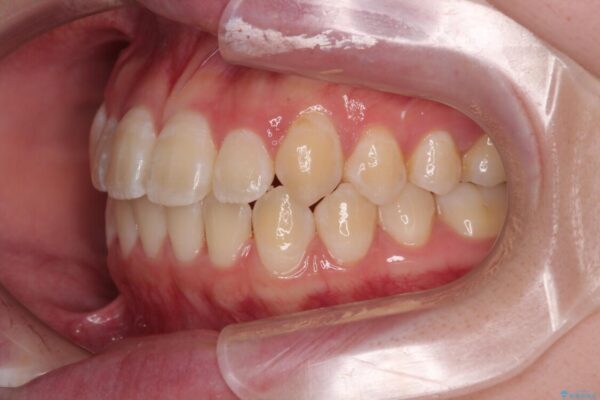

「前歯のデコボコ(叢生)をきれいに整えたい」とのことでご来院されました。

治療前

• 【モニター】前歯のデコボコをスッキリ解消!目立ちにくいワイヤー矯正でスピーディに治療完了 治療前画像